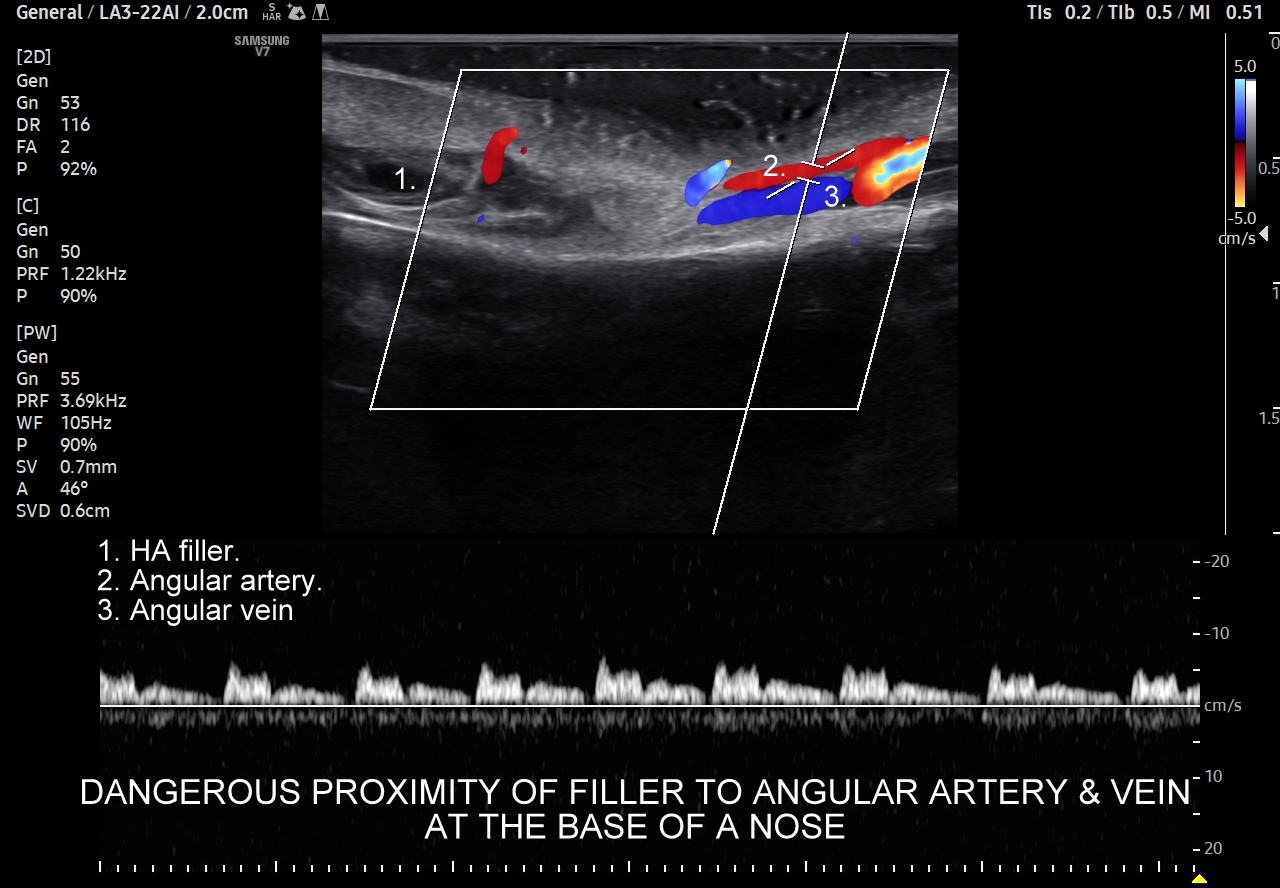

Przykładowo tętnica kątowa będąca przedłużeniem tętnicy twarzowej, poprzez tętnicę nadbloczkową i oczodół ma połączenie z tętnicą oczną oraz wewnątrzczaszkowym odcinkiem tętnicy szyjnej wewnętrznej. Z tego powodu nieopatrzne podanie wypełniacza do tętnicy w obrębie twarzy podczas zabiegu z zakresu medycyny estetycznej może skutkować przedostaniem się egzogennego materiału do tętnicy środkowej siatkówki lub tętnicy zaopatrującej mózg, a przez to wystąpieniem nagłej ślepoty albo udaru mózgowego.

Należy również podkreślić, iż ze względu na gęste upakowanie naczyń, bezpośrednią bliskość anastomoz i często obecność szerokiej, acz niewidocznej żyły kątowej szczególnie niebezpiecznym w aspekcie deponowania wypełniaczy czy wystąpienia lokalnych stanów zapalnych jest obszar u nasady nosa, przy wewnętrznych kącikach oczu i na gładzinie (łac. glabella). Na załączonych do artykułu skanach zobaczyć można czym jest trójkąt śmierci na twarzy i na tej podstawie uzmysłowić sobie, dlaczego tak właśnie się nazywa. Proszę zwrócić uwagę na przykład ekstremalnej bliskości nieodpowiedzialnie zdeponowanego u podstawy nosa wypełniacza, tu kwasu hialuronowego, w stosunku do struktur naczyniowych.